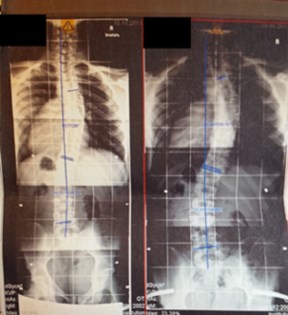

Das Röntgenbild vom November 2011 ist etwa 6 Wochen nach der Kur in Bad Salzungen geschossen worden. Mit 26° thorakal war das mein bester Wert, den ich je hatte. Leider bin ich dann wieder auf das Anfangsniveau von 34° thorakal zurück gefallen, trotz Korsett von cctec und ca. 120 Minuten Schroth-KG pro Woche. Ich muss dazu noch sagen, dass ich von Oktober 2010 bis November 2011 ein Korsett von Rahmouni getragen habe, allerdings nur etwa 8 Stunden am Tag, und die auch nicht am Stück. Das Korsett von cctec habe ich im Schnitt auch nur 8-10 Stunden pro Tag getragen. Aus privaten Gründen trage ich es seit Dezember 2013 nur noch sehr unregelmäßig, manchmal 3 Tage am Stück gar nicht, dann wieder 8 Stunden.

Mein Ziel war es immer gewesen, sowohl den Cobb-Winkel zu reduzieren als auch meinen Rücken zu symmetrisieren. Ersteres hat nicht geklappt. Und das zweite Ziel auch nicht wirklich. Der thorakale Skoliometer-Wert mag ein wenig geringer geworden sein, und die Hautfalte an der schwachen Stelle etwas unscheinbarer, aber ich bin immer noch krumm. Und ich fürchte, dass sich das mit konservativen Behandlungen bei mir auch nicht ändern wird. Immerhin sind Dr. Wilke und Herr Nahr mit meinem Rücken zufrieden.